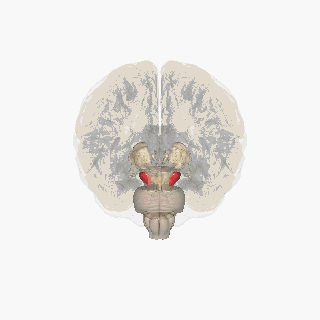

![]() Substantia nigra highlighted in red. | |